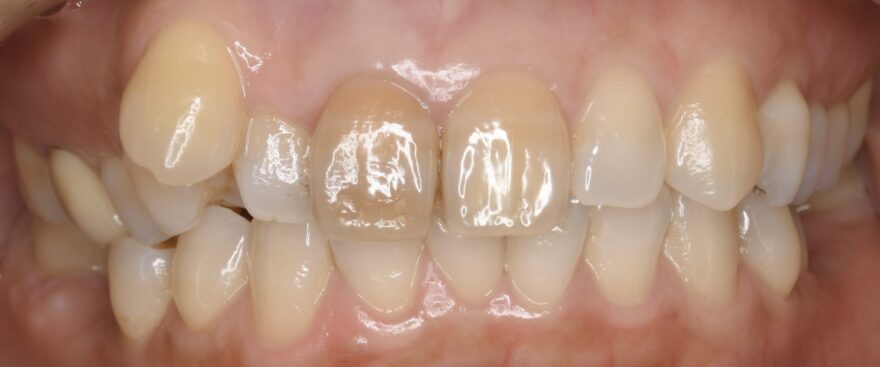

初診時の口腔内写真

左上の八重歯を抜くことで、よりバランスが取れた美しさになりました。